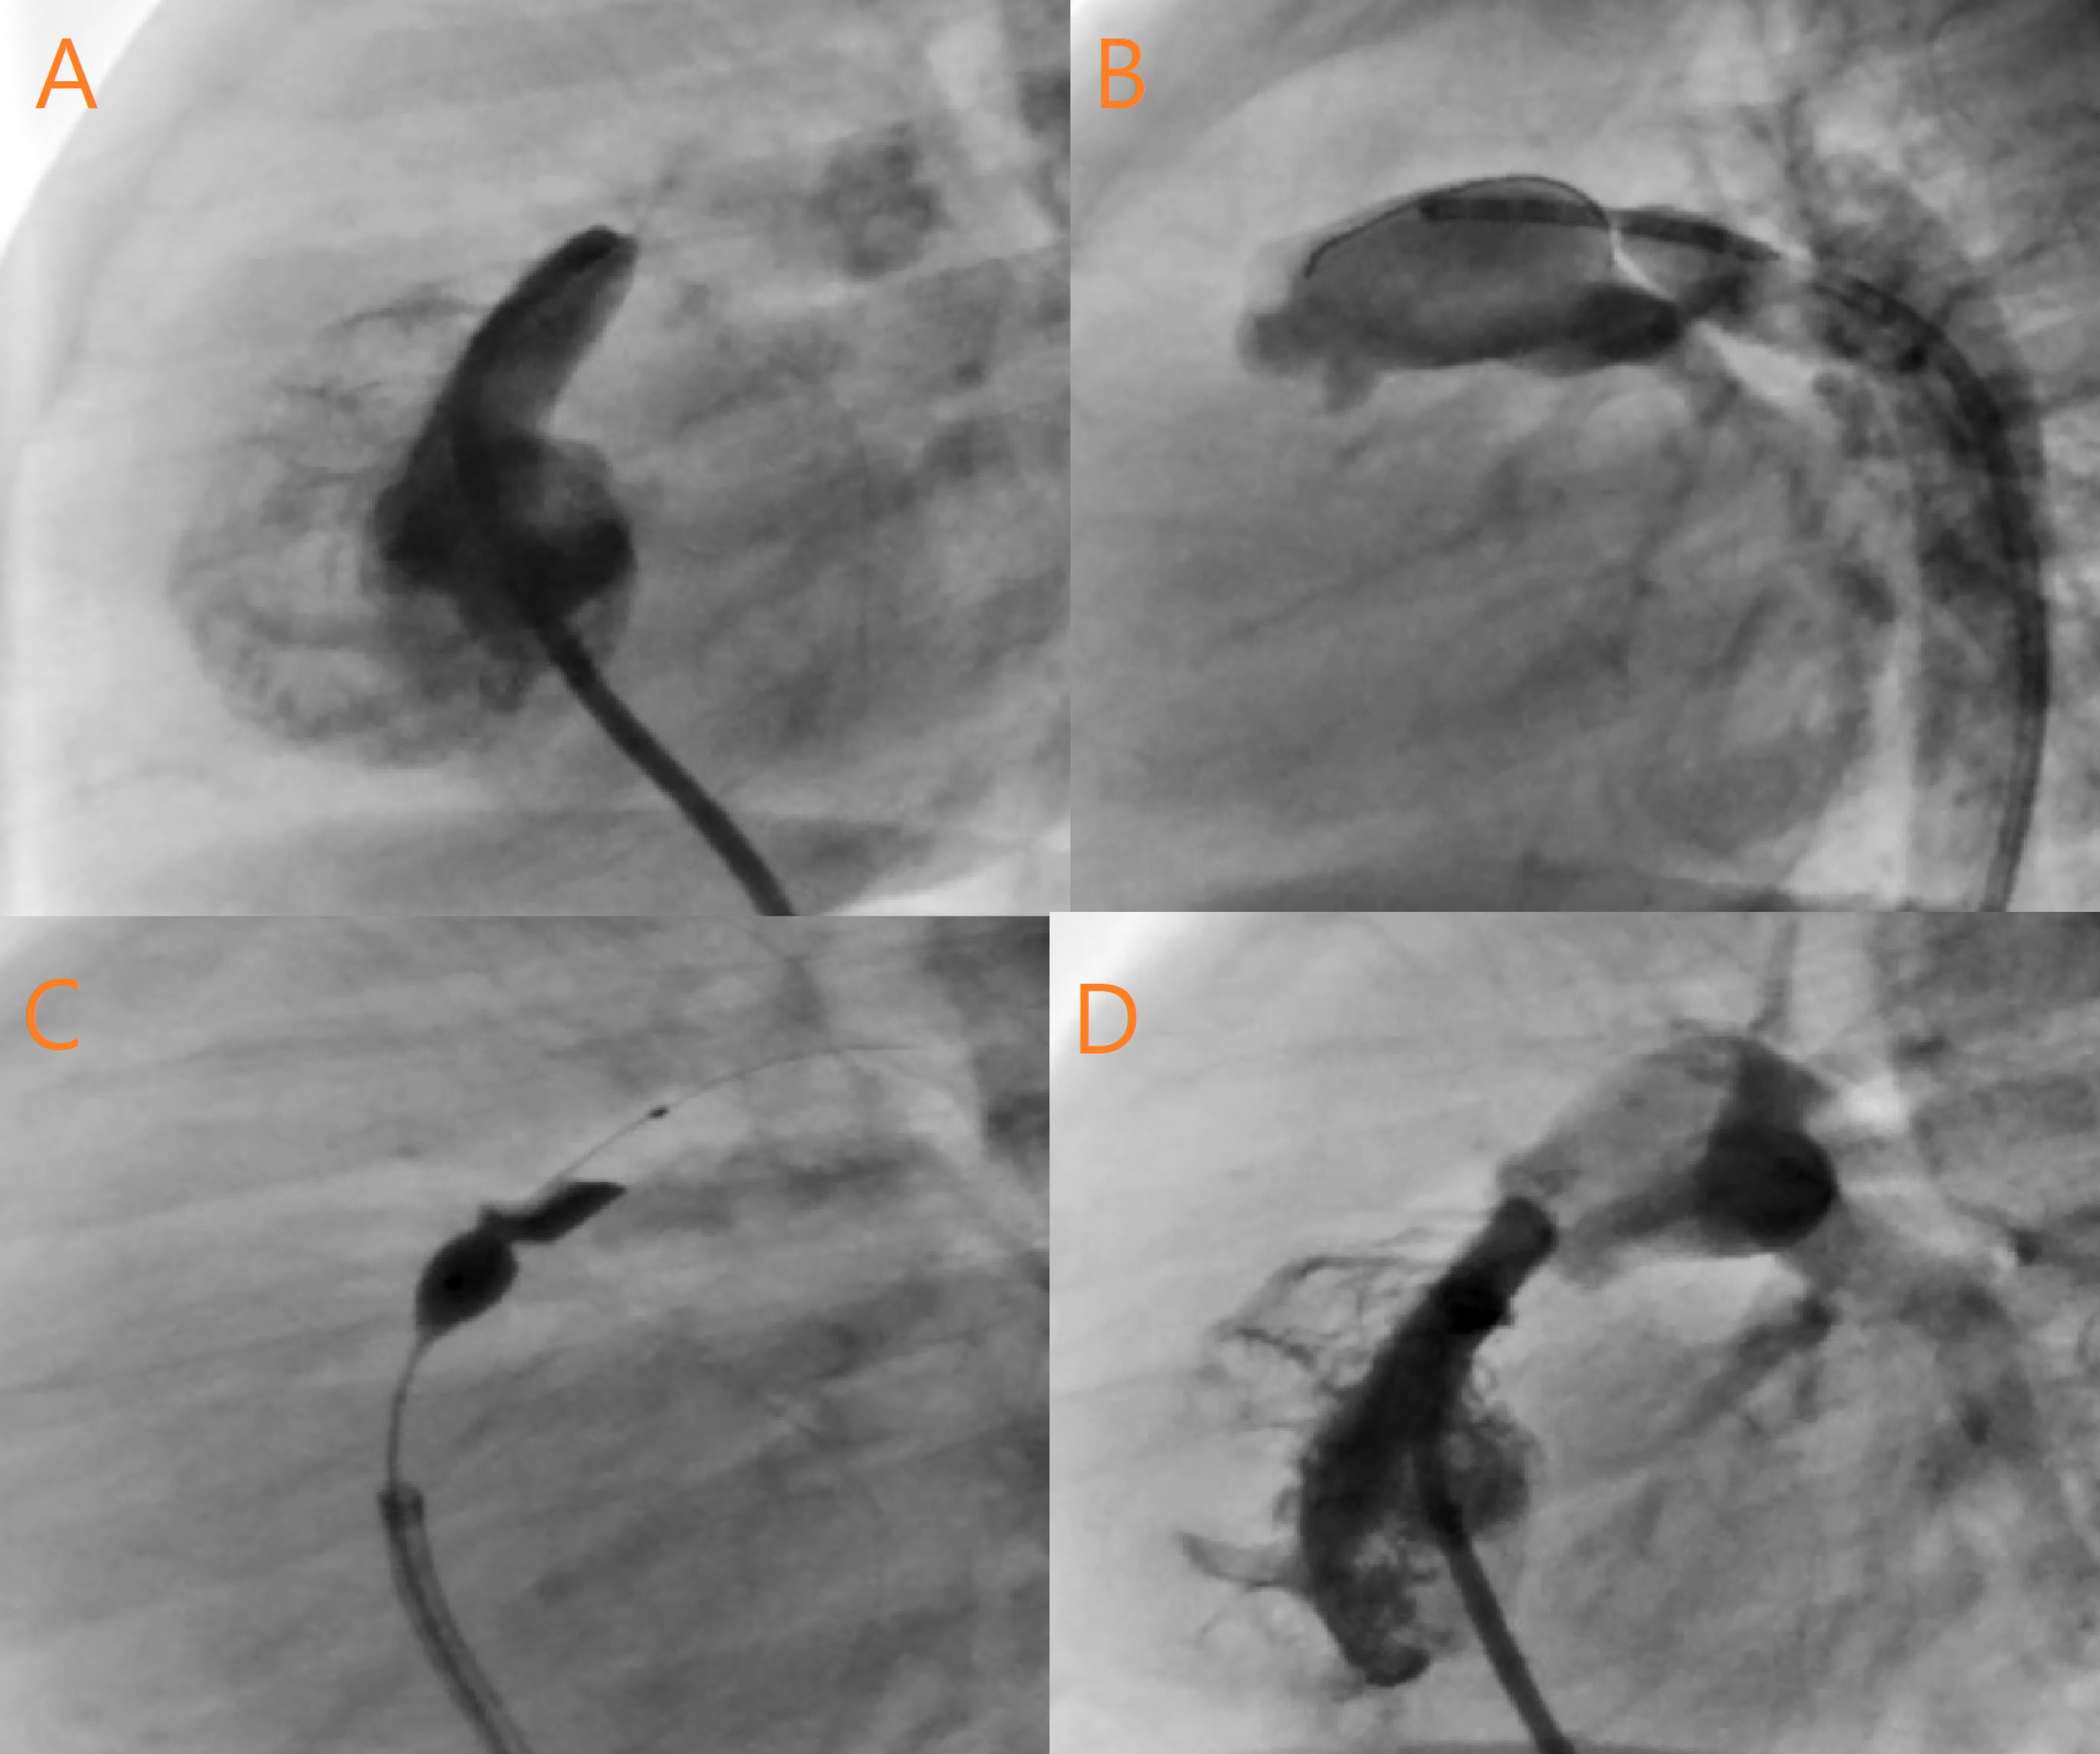

The BPV procedure was considered successful if the guide wire and the intended pulmonary balloon were successfully passed through the pulmonary valve and an appropriate waist was formed ().

jcvtr-13-156-g001

Figure 1. A: RV injection in Lateral view revealed Critical Valvar PS, Sever RVH,Small size RV,Elongated RVOT, Pin hole Fenestrated Pulmonary Valve, Doming and Thickening of Cusps. B: DAO injection in Lateral View showed Tubular and long shape PDA, Significant Left to Right Shunt,PA filling via PDA. C: Ante grade wiring of PA by CTO wire, PTPC by Mini- Tyshak Balloon size 7-20 mm. D: Final injection in RV at Lateral View showed opening of Pulmonary Valve, Patent and good ante grade Flow.